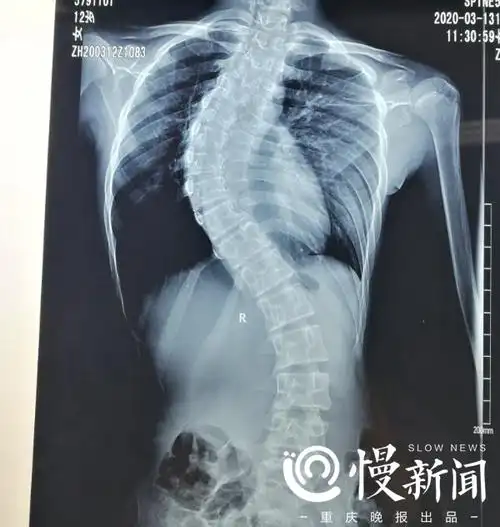

13岁漏斗女孩无法走路仍盼继续上学

看看这小姑娘弯腰驼背的,影响了生活和学习

因为这个细节女孩躺上手术台80宝宝驼背和他有关

双肩不等高,驼背不是小事 这会让孩子"矮人一等"

比杨幂驼背更吓人的,竟是阿娇的"脊柱侧弯"?